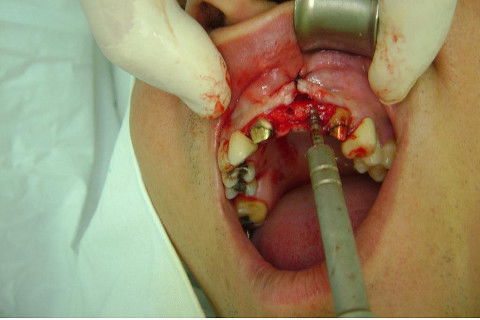

Cirurgia realizada hoje de manhã...No planejamento percebi medindo espessura do rebordo com especímetro que as medidas não estavam muito boas, ou o ideal, em torno de 4,5 a 5 mm ate´o terço médio do rebordo e melhorava no final, com 6 a 7 mm. Optei então por uma pequena expansão usando os expansores rosqueáveis. Aconteceu uma pequena fenestração na hora da fixação dos implantes, especialmente na região do 22 que fraturou o início da tábua óssea, mas não me preocupei porque não foi mais do que 2 mm de fratura em direção apical, o implante ficou infraósseo e com boa estabilidade (60 N no 21 e 40 N no 22). Esta fratura tb não deixou osso completamente solto, foi do tipo galho verde, deixei em posição e suturei normalmente. Só não fiz e nem estava planejado carga imediata mesmo, mais pelo motivo da oclusão inadequada do caso.

Fotos do caso